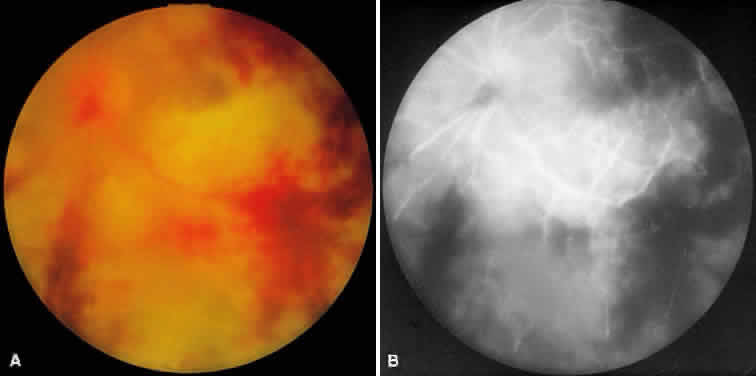

ARN is characterized by a retinal vasculitis affecting both the arteries and veins in the fundus, which is manifested by sheathing of the larger vessels (Fig. 2).7–10,16 Initially, patchy areas of peripheral retinal whitening (“thumbprint lesions”) representing full-thickness retinal necrosis are present or develop shortly after the vasculitis (Fig. 3). During a course that may span days or weeks, these patches coalesce into geographic areas (Fig. 4A). The entire peripheral retina (360 degrees) may be involved, or, more commonly, there are several noncontiguous patches of necrosis, each covering from a half to three clock hours (Figs. 5 and 6). The posterior segment lesions may not be detected without examination of the peripheral retina.

As the infection progresses, the leading edge of confluent retinal whitening advances toward the posterior pole (Fig. 7A). The retinitis may not progress posteriorly to the vascular arcades, sparing the macula and central vision. It is hypothesized that the retinal necrosis in ARN results from the combined effect of intracellular viral replication with subsequent cell death and vascular occlusion secondary to acute vasculitis. In some patients, the retinal vasculitic component may be much more prominent than the retinal necrosis.7 Optic disc swelling, either hyperemic or pallid, is a common feature of the ARN syndrome.1 Perivascular hemorrhages may be present (Fig. 8); however, widespread areas of retinal hemorrhage are atypical. Retinal vascular occlusion, often involving the arteries, can occur at any point during the clinical course. Without treatment, the inflammatory component of ARN typically burns out in 6 to 12 weeks, leaving behind a thin atrophic retina with associated pigmentary changes.10

Intravenous fluorescein angiography may be helpful in delineating the extent of infection and elucidating the cause of central visual loss. In the early frames, choroidal perfusion defects may be seen; these defects are caused by areas of focal choroidal inflammatory cell accumulation and overlying retinal pigment epithelial damage (Fig. 16). Such choroidal perfusion defects may occur away from zones of active necrosis.42 Acute obstruction of the central retinal artery or any of its branches may be present. Peripheral views in the areas of active retinitis commonly show little or no intravascular fluorescein in the retinal arteries and veins. Often an abrupt “cut-off” of the intravascular fluorescein may be apparent at the edges of the retinal inflammation (see Fig. 4B and C). Areas of active retinitis show blockage of the underlying choroidal fluorescein pattern (see Fig. 7B). Recirculation phase views may reveal macular leakage, optic disc, and retinal vasculature staining.